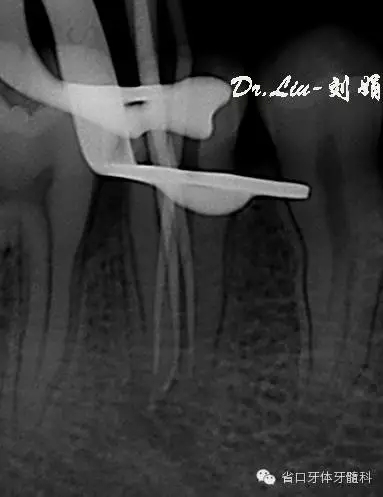

牙片顯示:45充填物至髓腔,根管內(nèi)無充填物影像,根管影像不清疑似多根管,根尖區(qū)見X線透射區(qū)。

圖1:術(shù)前X線片,根管影像不清,根尖區(qū)見X線透射區(qū)

圖5:術(shù)中插尖片,見3根管